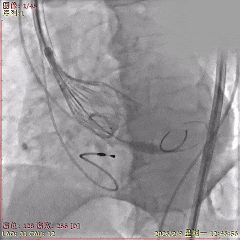

术中影像

初始造影确定无冠窦

第一次释放,瓣膜位置稍高

回收后再次释放,瓣膜位置可

多角度评估,确认瓣膜稳定

瓣膜稳定脱钩,无位移

脱钩后造影,瓣膜位置可,无瓣周漏